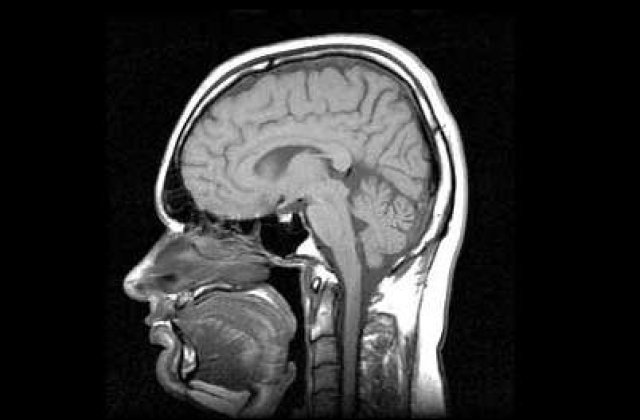

Un experiment stiintific realizat de un grup de cercetatori din cadrul Universitatii de la Tel Aviv au introdus cipuri electronice in locul unor zone “defecte”ale unor creiere functionale de cobai.

Cercetatorii au reusit sa creeze circuite care pot inlocui functii precum clipitul si sa le implanteze in creierele sobolanilor de laborator, potrivit dailymail.

Echipa din cadrul universitatii islaeliene considera ca studiilor si dezvoltarea proiectului va duce la ajutarea persoanelor care sufera de malformatii ale creierului, cum ar fi cele determinate de boala Parkinson, prin inlocuirea tesutului deteriorat cu cipuri electronice care sa indeplineasca functia respectiva.